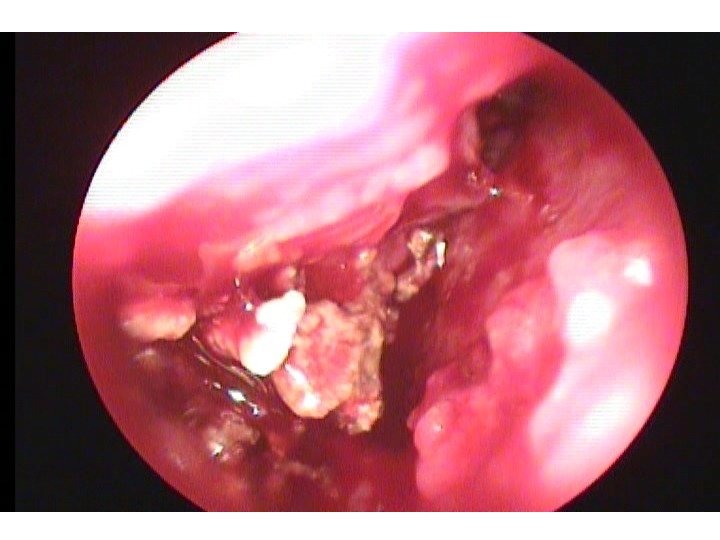

ALLERGIC FUNGAL SINUSITIS (AFRS) • Non-invasive – local fungal hyphae in the mucin – allergic response to the fungus – polyps with thick grey to brownish “greasy” mucin drainage

ALLERGIC FUNGAL SINUSITIS (AFRS) • Invasive – Microscopic invasion of fungus in the mucosa – Necrotic black tissue with nonpainful debridement is an emergent life threatening fungal infection – mucomycosis

SURGICAL TREATMENT • Image guided endoscopic sinus surgery • Balloon sinuplasty